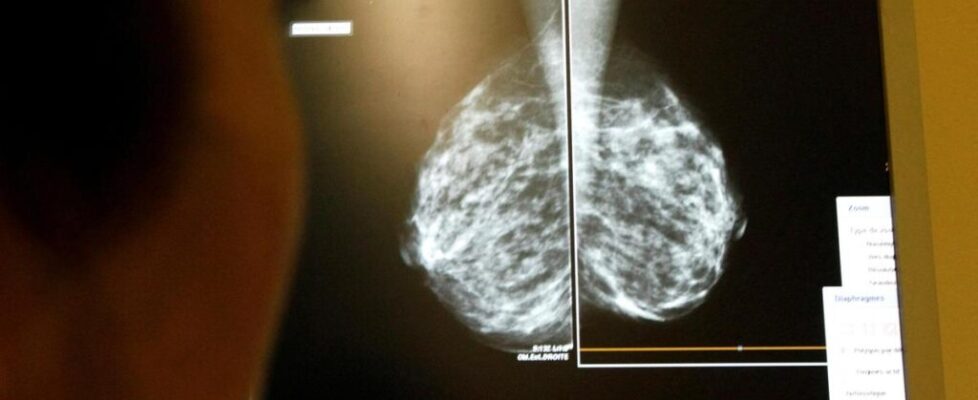

Nearly 13% of women in India with breast cancer experienced metastasis: Study

Study demonstrates that metastatic presentation in India is strongly influenced by tumour size, grade, nodal involvement, and lympho-vascular invasion, with health system context modulating the risk